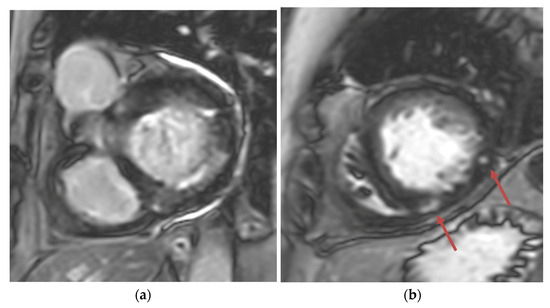

Figure 3.

(a) Short-axis phase-sensitive inversion recovery showing patchy subendocardial late gadolinium enhancement in basal inferolateral wall; (b) Short-axis phase-sensitive inversion recovery showing patchy intramyocardial late gadolinium enhancement (red arrows).

Transthoracic echocardiogram (TTE) showed severe asymmetric left ventricular hypertrophy, preserved left ventricular ejection fraction at 65–70%, systolic anterior motion (SAM) of the mitral valve (Figure 1 and Supplementary Video S1), left ventricular outflow tract (LVOT) obstruction with a peak velocity of 7.1 m/s at rest and an eccentric, posteriorly directed mitral regurgitant jet (Figure 2). Pharmacological myocardial perfusion SPECT with gated imaging was obtained one year prior to presentation and showed normal myocardial perfusion, left ventricular volume and systolic function. Cardiac magnetic resonance imaging showed left ventricular hypertrophy with a maximal thickness of 1.7 cm at the mid-ventricular septum and late gadolinium enhancement in the lateral and inferior half of the left ventricle, the basal inferolateral wall, the apical lateral walls and the apical anterior wall (Figure 3a,b). These findings were consistent with a diagnosis of HCM with outflow tract obstruction; thus, the patient was started on beta blockers.